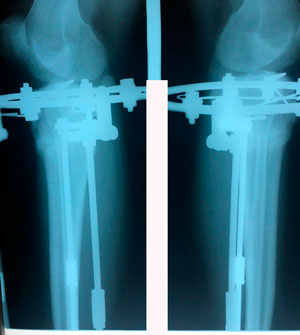

Исходник - 14 лет.

Дата операции - 20.03.2020

Дата снятия аппаратов - 11.06.2020

Срок сращения - 83 дня.